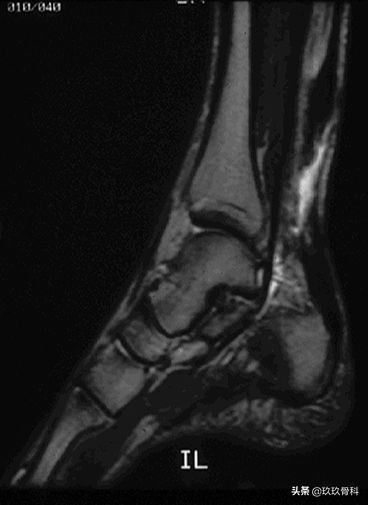

MRI

跟腱撕裂 MRI评价标准:

(1)完全撕裂:跟腱增粗,腱束分离,局部T1WI、 T2WI信号均匀增高或局部信号不均匀增高,腱束重叠交织但不连续 (2)部分撕裂:跟腱增粗,局部T1WI、T2WI信号不均匀增高,内见部分连续的腱束影。